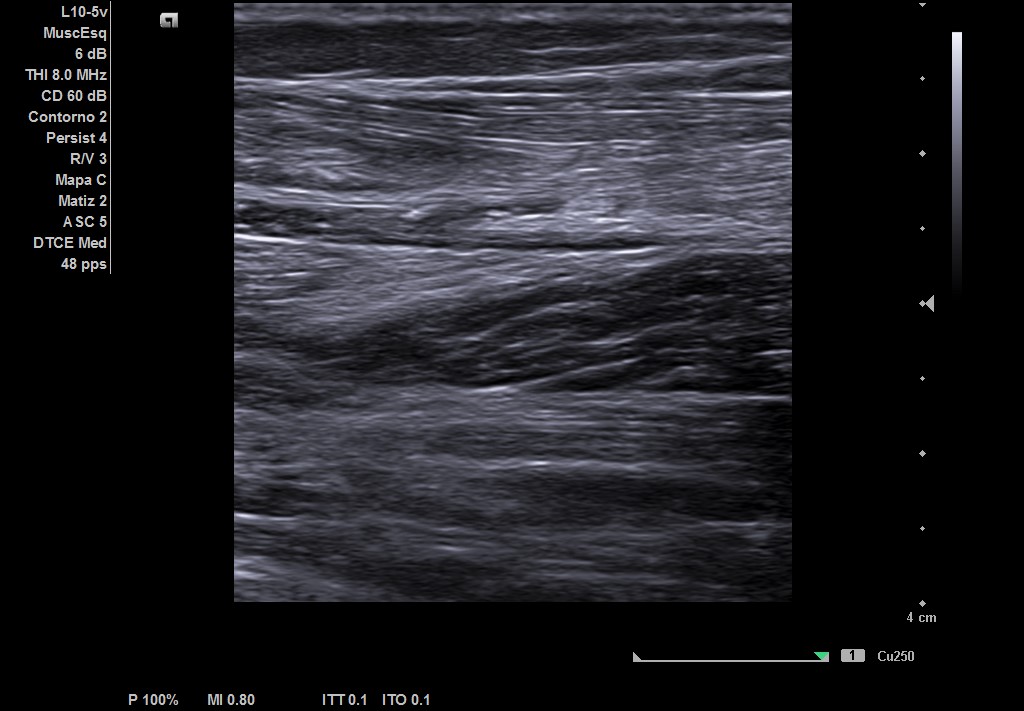

Descripción de los hallazgos ecográficos y las imágenes más relevantes para la resolución del caso

Ecografía musculoesqueletica: se objetiva signos de rotura de inserción gemeral interno-soleo de 21 x 32 mm y línea de líquido en zona superior intergastronemios de 1 mm de grosor. Doppler negativo.

Ante estos hallazgos realizamos seguimiento en consulta para valorar evolutivamente la lesión e iniciar fisioterapia precozmente.

En el trascurso de este proceso, con ayuda del fisioterapeuta, valoramos la consecución de objetivos, observado un desarrollo adecuado.

Después de 2 meses el paciente se encuentra asintomático habiendo recuperado completamente su funcionalidad. Y volviendo a practicar deporte de forma habitual.